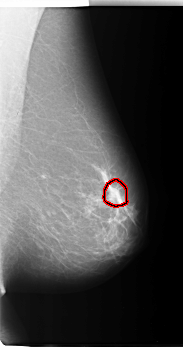

C_0040_1.LEFT_CC

LEFT_CC LINES 4728 PIXELS_PER_LINE 2656 BITS_PER_PIXEL 12 RESOLUTION 50 OVERLAY

FILE: C_0040_1.LEFT_CC.OVERLAY

TOTAL_ABNORMALITIES 1

ABNORMALITY 1

LESION_TYPE MASS SHAPE IRREGULAR MARGINS SPICULATED

ASSESSMENT 5

SUBTLETY 5

PATHOLOGY MALIGNANT

TOTAL_OUTLINES 1

BOUNDARY